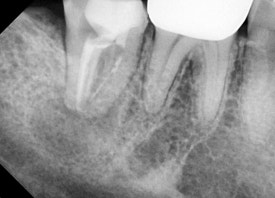

타원에서 받은 신경치료에 염증이 재발해서 재신경치료를 시행한 사례입니다.

일반 신경치료 뿐 아니라

염증이 재발한 신경치료를 다시 하는 것도 좋아합니다.

어려운 케이스는 미세현미경의 도움으로 섬세하게 접근하거나,